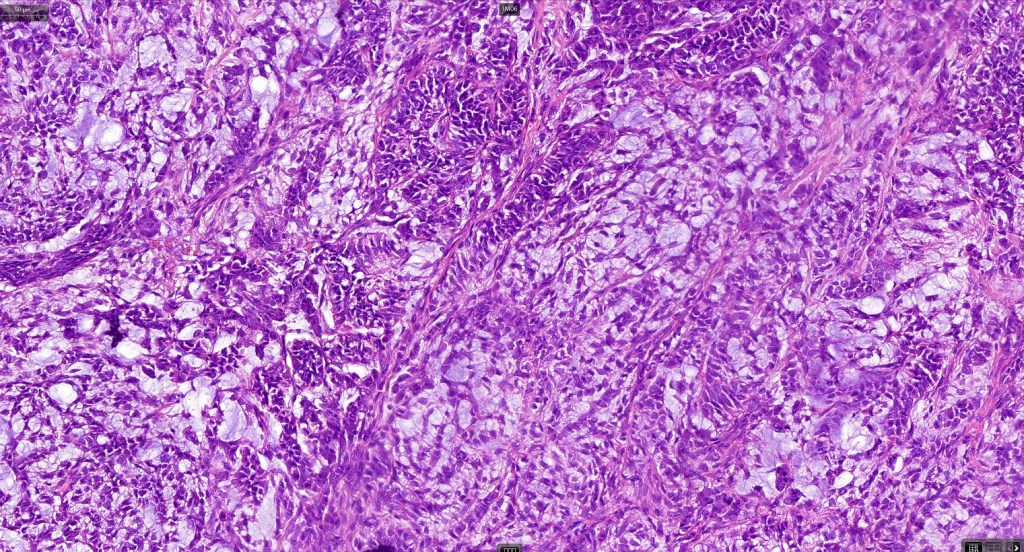

Histological features

•Pure population of myoepithelial cells dispersed in sheet-like, reticular, whorled or fascicular patterns in a myxoid or hyaline stroma

•Cell types include epithelioid, spindled, histiocytoid & plasmacytoid

•No pleomorphism and absent or scanty mitoses

•Syncytial myoepithelioma characterized by sheet-like growth of ovoid to spindle cells with pale cytoplasm, syncytial borders & vesicular nuclei

•In malignant myoepithelioma there is an infiltrating border, marked pleomorphism, high mitotic rate & necrosis. Perineural infiltration & lymphovascular invasion may be seen